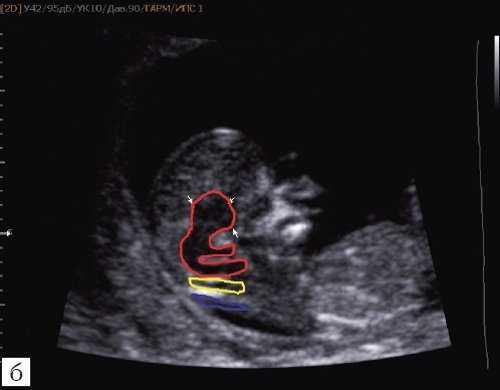

а) На эхограмме:

1 - ствол мозга;

2 - интракраниальное пространство, или IV желудочек;

3 - большая цистерна головного мозга;

4 - воротниковое пространство.

б) Вид "осьминожки":

- красный цвет - диэнцефалон (таламус), со стволом мозга (верхняя ножка) и IV желудочком (нижняя ножка);

- желтый цвет - большая цистерна головного мозга;

- синий цвет - воротниковое пространство.

Новый ультразвуковой маркер в изучении нормальной ультразвуковой анатомии головного мозга плода в срок 11-14 недель беременности

Особенности визуализации изложенных выше структур в данном сроке позволили нам выделить и назвать новый ультразвуковой маркер нормальной ультразвуковой анатомии мозга плода. Структуры головного мозга плода в этой области схожи с осьминогом, у которого есть голова и две приблизительно равновеликие по диаметру ножки, представляющие собой ствол мозга и IV желудочек. Ниже ножек "осьминожки" визуализируется 2 "подушки осьминожки" - это два анэхогенных пространства - большая цистерна и воротниковое пространство (рис. 2, б).

Так как речь идет о сроках первого скрининга, т.е. раннего осмотра, новый ультразвуковой маркер мы назвали "осьминожкой" (рис. 3).

а) Стрелками указана голова "осьминожки" - диэнцефалон (таламус).

б) Красный цвет - диэнцефалон (таламус), со стволом мозга (верхняя ножка) и IV желудочком (нижняя ножка); желтый цвет - большая цистерна головного мозга; синий цвет - воротниковое пространство.